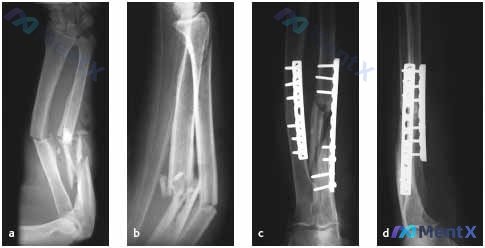

看到一个很典型的前臂高能量损伤病例,结合影像和分析报告,整理一下思路。 --- 病例基本情况 - 患者:25岁男性 - 损伤:高能量致前臂外伤 - 影像:术前(图a、b)+ 术后(图c、d)X光 核心影像表现 术前: - 尺骨与桡骨骨干中远段均可见骨折 - 尺骨为斜行/粉碎性骨折,断端移位明显,伴成...